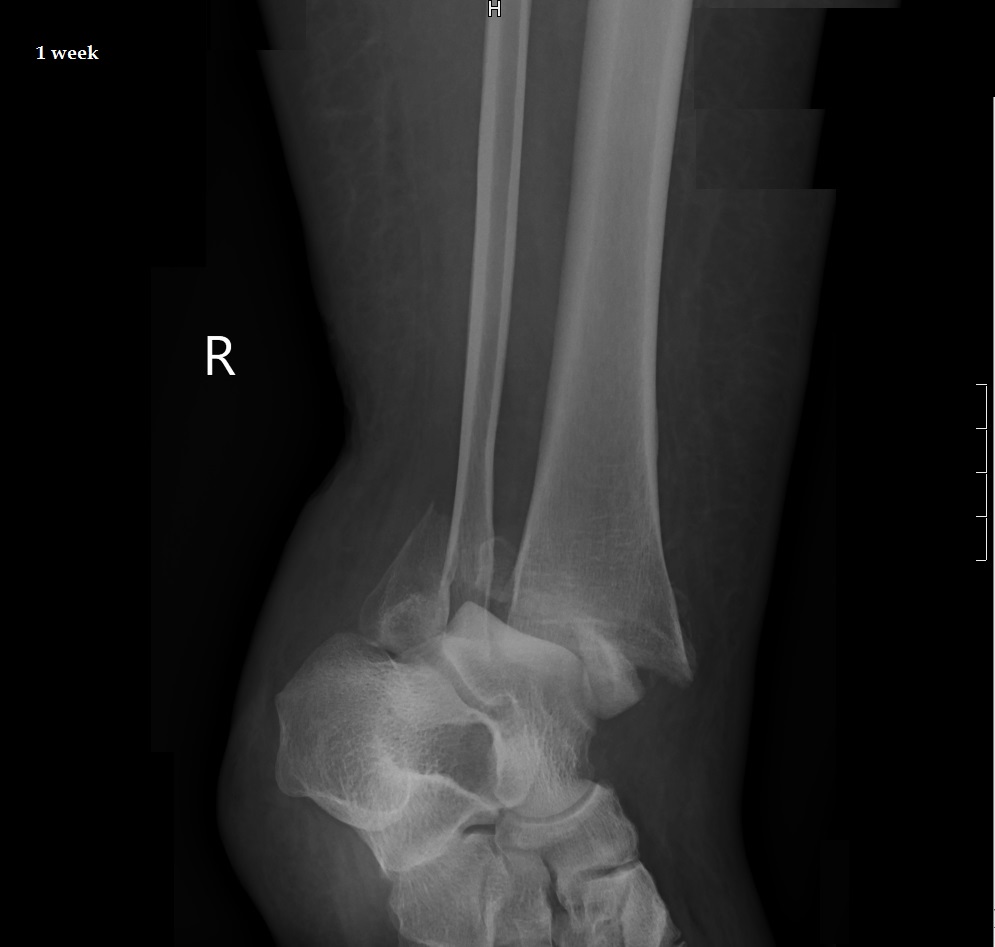

From stock.adobe.com

Xray image of ankle fracture , broken ankle , pott fracture fix by open surgery and metal plate How To Shower With An Ankle Fracture Apply an ice pack 20 minutes of every hour, you are awake, for the first 2. Sit with your foot elevated higher than your knee at least 4 times a day. After 10 to 14 days, the sutures are removed. For the first couple of weeks, patients are in a splint and are elevating the limb 90% of the day.. How To Shower With An Ankle Fracture.